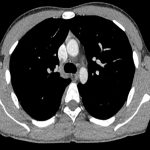

Чаще всего ЭГЭ поражает конечности (65%), но 8% «прячется» в средостении. Именно «прячется», потому что долго заболевание протекает, как правило, без каких-либо признаков, а обнаруживают его практически всегда случайно.

В отделении торакальной хирургии МНИОИ им. П.А. Герцена филиала НМИЦ радиологии Минздрава России проведено несколько успешных операций. У 56-летней пациентки диагностирована ЭГЭ правой плечеголовной вены, у 23-летнего мужчины нашли ЭГЭ непарной вены. Эти опухоли редкие среди редких, практически единичные случаи, и для их лечения нужны специалисты экстра-класса. Метод хирургического вмешательства дал положительный результат: обе операции прошли успешно, хотя и были сопряжены с большим риском нарушения кровотока.

«Операции подобного типа относятся к категории повышенной сложности. И этому есть несколько причин, рассказывает заместитель генерального директора по хирургии НМИЦ радиологии Минздрава России д.м.н. Андрей Рябов. Например, в первом случае опухоль располагалась внутри просвета самого сосуда, поэтому мы не могли сделать предварительную биопсию и провести морфологический анализ раковых клеток». Уже во время операции хирурги констатировали, что опухоль локализована в области слияния плечеголовных вен и распространилась на верхнюю полую вену и клетчатку переднего средостения.